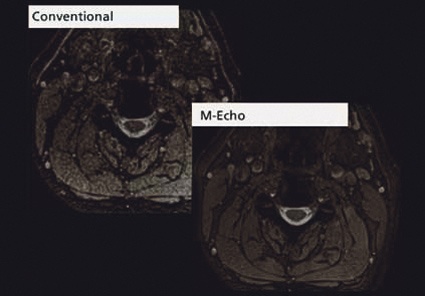

Dies ist sicherlich eine Forschungskooperation, in der es sinnvoll ist, auch die 32-Kanal-Kopfspule einzusetzen und beim Optimieren das letzte Quäntchen Signal auszuschöpfen, wie es auch bei der funktionellen Bildgebung genutzt wird. Eine in der Routine viel häufigere Anwendung wird dagegen eine neue T2-FSE-Sequenz für die Wirbelsäulenbildgebung haben, die unempfindlicher auf Flussartefakte ist und wie die neue mEcho für die transversale T2*-Bildgebung schnell im nächsten Software-Release zur Verfügung steht. Zusammen mit der 3D-DIR-Sequenz sind es dann drei Neurosequenzen, die schnell ihren Weg von der Entwicklung in die Routine finden.

Neben verschiedensten neuen Sequenzen und Techniken realisiert Toshiba beim Titan 3T seine neue, verbesserte Metallartefaktreduktions-Technik mART. Diese wird gerade auch bei Patienten der Wirbelsäulenchirurgie eingesetzt, bei denen die typischen „sternförmigen“ Artefakte eine Beurteilung der Wirbelkörper meist unmöglich gemacht haben und eine Beurteilung des Myelons oft erschwerten. Mit dem neuen mART-Verfahren kommt es im Vergleich zu konventionellen MRT-Aufnahmen zu einer Messzeitverlängerung von ca. 30 %. Dies ist dramatisch kurz, da bisherige Metallartefaktreduktions-Sequenzen mit ähnlicher Bildqualität etwa 300 % der herkömmlichen Scanzeit benötigten. Diese Entwicklung ist gerade auch im Hinblick auf die Patientensicherheit wichtig, da die neuen mART-Verfahren somit auch einen Beitrag zur SAR-Reduktion leisten.